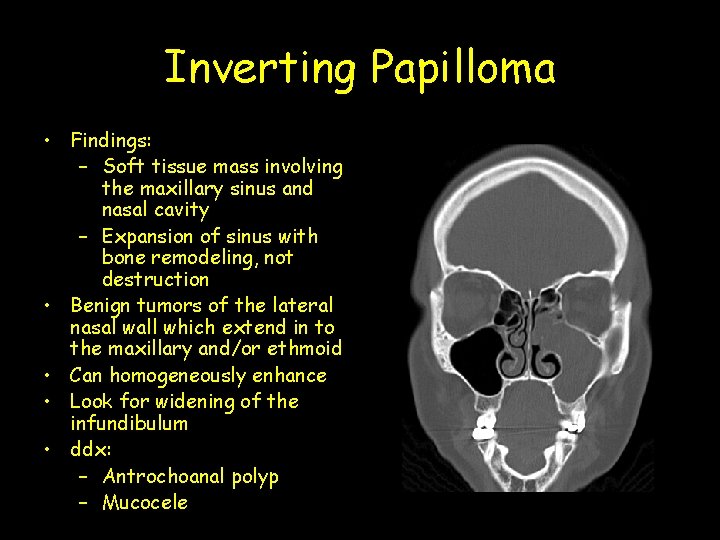

Inverting Papilloma • Findings: – Soft tissue mass involving the maxillary sinus and nasal cavity – Expansion of sinus with bone remodeling, not destruction • Benign tumors of the lateral nasal wall which extend in to the maxillary and/or ethmoid • Can homogeneously enhance • Look for widening of the infundibulum • ddx: – Antrochoanal polyp – Mucocele